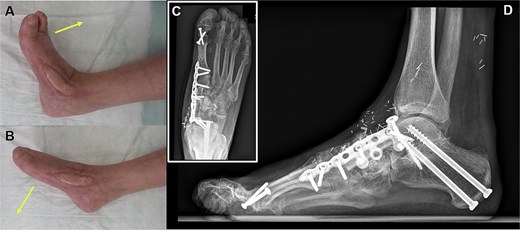

The orthoplastic approach involved subtalar arthrodesis and the use of a 3.8 cm vascularized free fibula graft from the contralateral leg to reconstruct the medial metatarsus (Fig. 2). The vascularized bone was placed between the talus and the distal remains of the medial cuneiform bone and fixed with a low-profile medial column plate (3.5 mm medial column plate, Arthrex Inc., Naples, FL), spanning from the talus to the first metatarsal (Fig. 3). The remaining dead space was filled with additional autologous cancellous bone. The free fibula flap was harvested together with a perforator-based 10 × 1.5 cm skin island, which was used to reconstruct the subsequent soft tissue defect (Figs 2 and 3). The microanastomosis was performed end to end to the dorsalis pedis artery and to the great saphenous vein (GSV) using a 2 cm vein graft from the GSV. Initial healing went uneventfully, but the patient repeatedly left the ward to smoke and failed to follow our training requirements for lower extremity reconstruction—placing the leg in a horizontal position for 5 days. Three days after surgery, we performed a revision of the venous anastomosis due to immediate venous flap congestion. Further partial skin grafting was performed on the skin island to address the transient volume increase of the flap. The further postoperative follow-up was successful, and the flap healed well (Fig. 3). Furthermore, the bone healed successfully. At the 12-month follow-up, the patient was able to walk without pain and with a full range of motion in the ankle (Fig. 4).

Six months after surgery, the final result shows a stable coverage with an adequate range of active motion regarding (A) dorsal extension and (B) plantar flexion. (C, D) The bone graft is fully integrated.